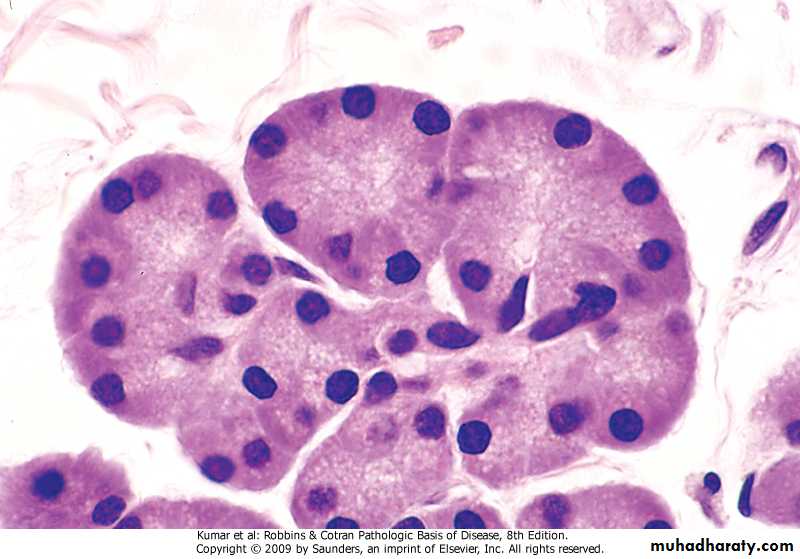

• Morphology -Grossly .well demarcated solitary or multiple nodules up to 30 cm in diameter .yellow-tan & frequently bile-stained . -Microscopy .sheets & cords of hepatocytes .no portal tracts, instead, prominent solitary vessels are present

Liver cell adenoma, sheets & cords of hepatocytes